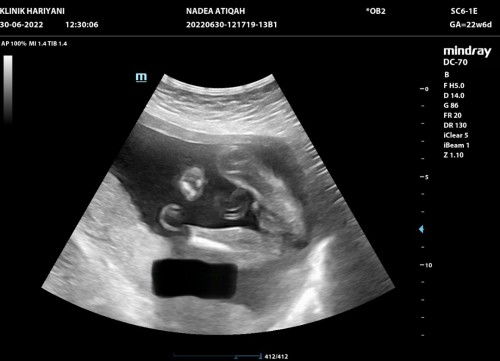

Doktor cakap awak baby apa ? Saya scan keluar ni haaa.. lepastu saya ni dah gelabah lepas banyak baca yang scan boy keluar girl 😂. Dah lah excited dah ni anak kedua boy. Awak semua pon nampak boy kan ? 😂😅

sye mcm ni jgk..tp nmpk pistol die dekt tepi ..die tk nk trpacak..sebb mlu😅

Mcm bby girl sbb tak 6pk belalai pun